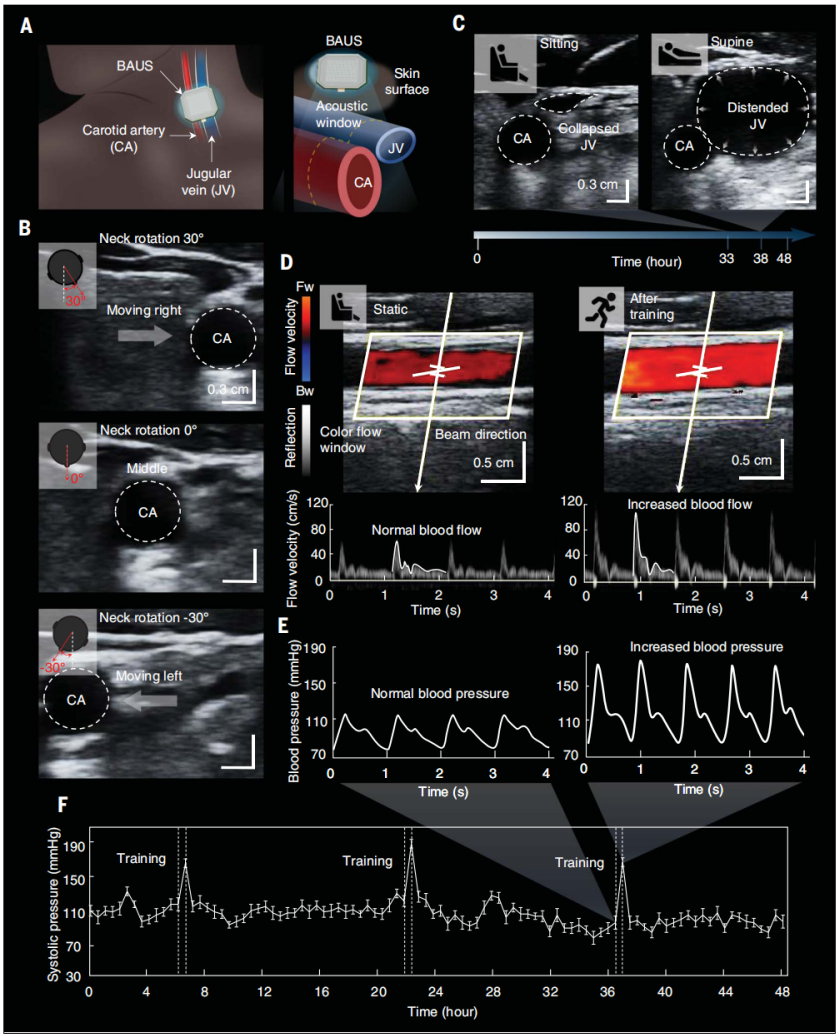

1.心脏疾病诊断:BAUS设备可以在动态身体运动(例如角度高达 ±30°的颈部旋转)下提供颈静脉和颈动脉的48小时连续成像(图3B)。这是BAUS设备在颈部的强大粘附力、BAUS探头的高成像分辨率以及 BAUS 探头孔径(2 cm x 1 cm)提供的大声学窗口等因素的共同作用结果。BAUS 成像结果显示,受试者的颈静脉直径从坐姿或站姿到仰卧位依次增加(图3C)。颈静脉直径的变化与右心房压力密切相关,因此可用于诊断心脏疾病,如心力衰竭和肺动脉高压。

2.血压监测:BAUS 成像结果进一步提供了颈动脉48小时连续血流速率和血压波形数据(图3,D至F)。例如,我们观察到受试者在0.5小时体育锻炼前后的血流率(从65到117 cm/s;图3D)和收缩压(从115到168mmHg;图3E)(数据采集和血压计算的详细信息见材料和方法)。此外,从0.5小时慢跑后测量的血压波形(图3E右图),我们可以看到每个心脏周期的收缩压峰值下降比运动前更陡,可能是由于运动引起的颈动脉血管舒张。

图3.血管长期连续BAUS成像